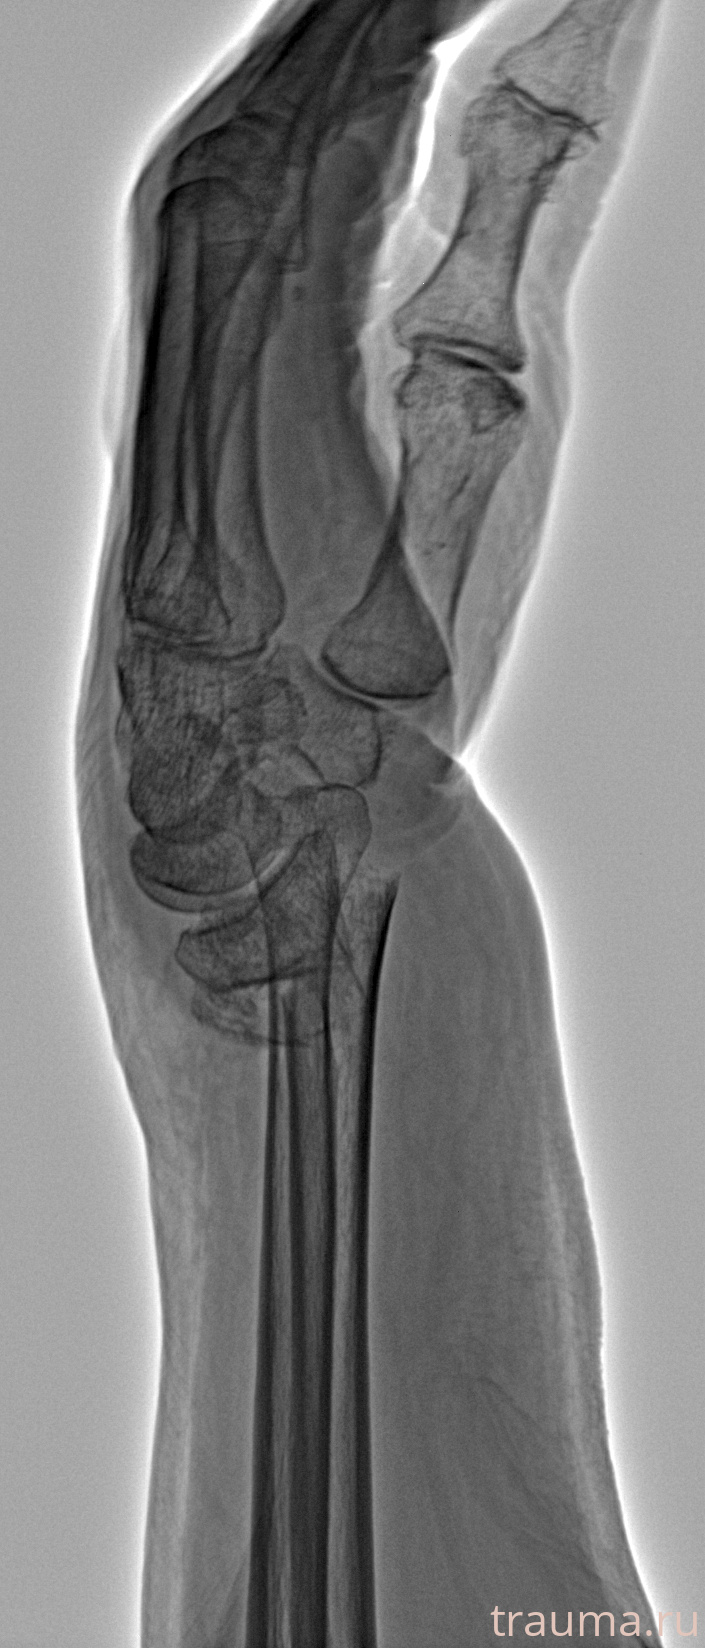

Рентгенограммы

Рентген на дому: по вашему адресу приезжает врач-рентгенолог, травматолог-ортопед с мобильным рентгеновским аппаратом, проводит диагностику травмы или заболевания, делает необходимые рентгенограммы, дает рекомендации по дальнейшему лечению. Получить качественные снимки в домашних условиях возможно благодаря уникальной методике, разработанной МосРентген Центром для института  Склифосовского